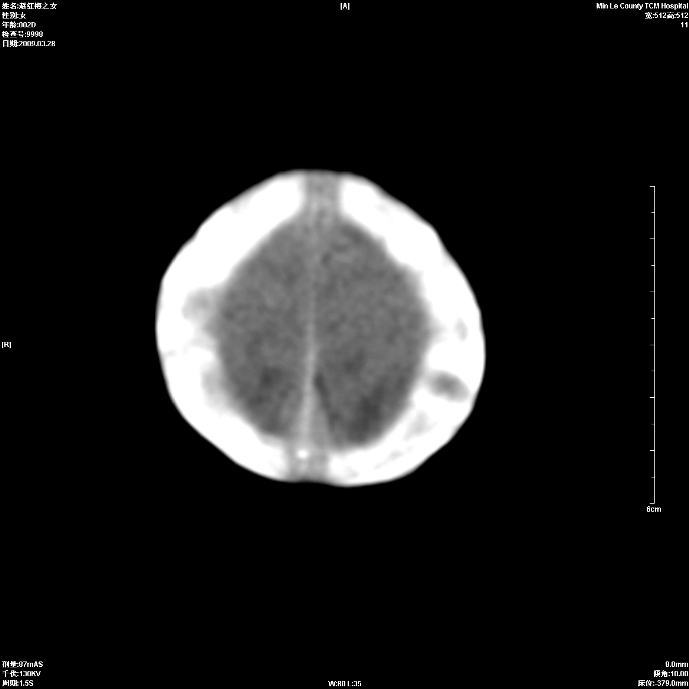

标题: PED1815:患儿出生两天,哭闹不安,囟门饱满 [打印本页]

标题: PED1815:患儿出生两天,哭闹不安,囟门饱满

少量蛛网膜下腔出血,有窒息史吗?

支持考虑新生儿缺血缺氧性脑病伴蛛网膜下腔出血,请结合临床,建议随访复查

缺血缺氧性脑病伴蛛网膜下腔出血.

支持缺血缺氧性脑病伴少量蛛网膜下腔出血。

支持 1)缺氧缺血性脑病。2)蛛网膜下腔出血。

z新生儿缺血缺氧性脑病,蛛网膜下腔出血!

若有窒息史,考虑缺血缺氧性脑病伴少量蛛网膜下腔出血。